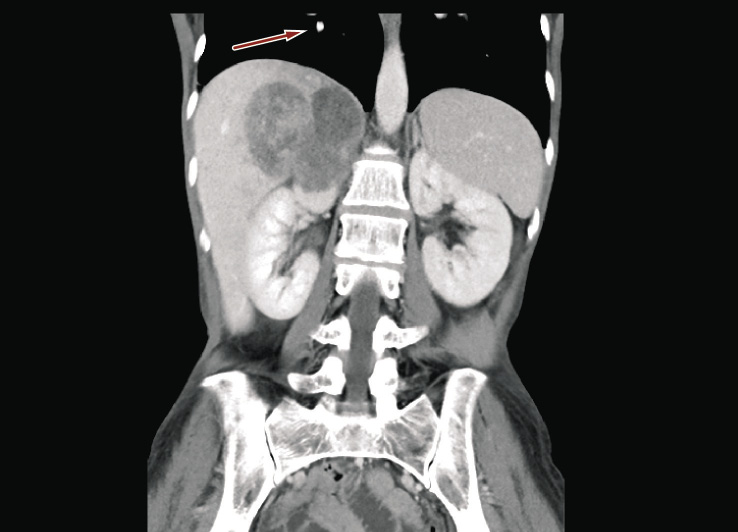

Physical examination revealed a tender palpable right upper quadrant mass. Laboratory studies were significant for anemia (6.2 g/dl) and leukocytosis (1.19 × 103/µl). Hormone panel including serum and urinary metanephrines, serum and urinary cortisol, plasma aldosterone, and serum adrenocorticotropic hormone was normal. Ten days after hospitalization, follow up chest-abdomen and pelvis CT scan revealed enlargement of the adrenal mass from 45 × 29 mm to 65 × 45 mm. New bilateral lung nodules were also noted (Figures 3 and 4).

Figure 4. CT scan showing evidence of lung metastasis (red arrow) in right pulmonary lobe (ten days after hospital admission)